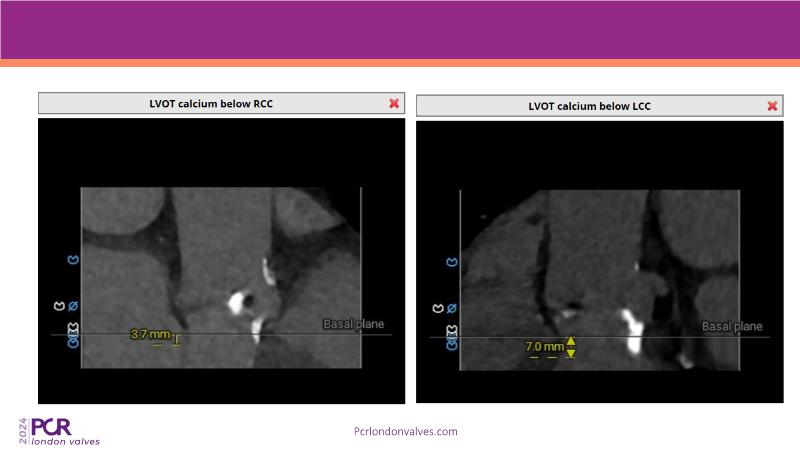

Watch this session to explore expert insights into best-in-class TAVI practices, from pre-procedural imaging and treatment strategy to procedural tips and post-procedural management. Learn from a compelling case study of an 88-year-old male patient with severe symptomatic aortic stenosis treated with the innovative MyVal Octapro THV. Discover key findings from the Landmark RCT sub-group analysis and delve into the unique scientific and design philosophy of MyVal Octapro, along with its real-world clinical potential.

- To learn from the experts best-in-the-class TAVI practice: pre-procedural (Imaging, sizing rationale, treatment strategy), procedural tips and tricks and post-procedural management